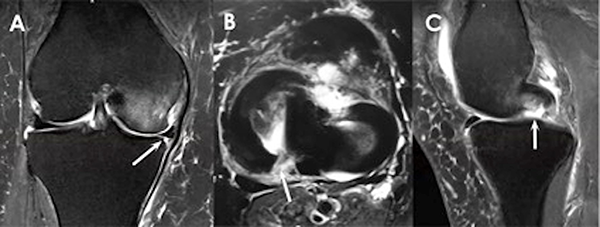

Los signos de resonancia magnética para las lesiones de la raíz del menisco medial incluyen:

Figura 4: Signos de resonancia magnética para las lesiones de la raíz del menisco medial. A) Extrusión meniscal medial de ≥3 mm en un corte coronal. B) Imagen hiperintensa en la región posterior de la raíz meniscal al evaluar un corte axial. C) El "signo fantasma", que es la ausencia de un menisco identificable en el plano sagital.